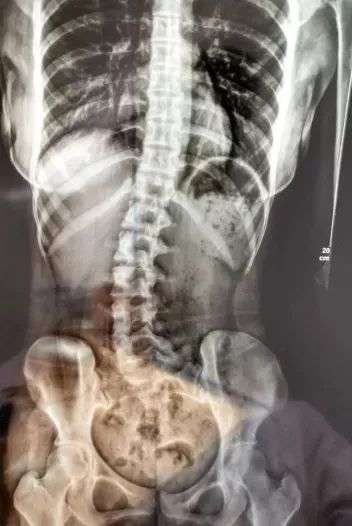

新闻中,广州18岁少女小邹,因腰痛、脖子酸等症状到医院就诊,检查发现脊柱严重侧弯。医生详细问诊得知,小邹习惯侧睡,且长期侧向右边。广州医科大学附属第三医院中医科主任医师胥海斌表示:“小邹长期不正确睡姿,使正常的脊柱逐渐失衡,从而发生侧弯。”

看到这里,睡觉也喜欢侧睡的小编,简直害怕极了!侧卧睡真的对脊柱有危害吗?那什么睡姿才正确?今天,小编一文解决你所有的疑惑。